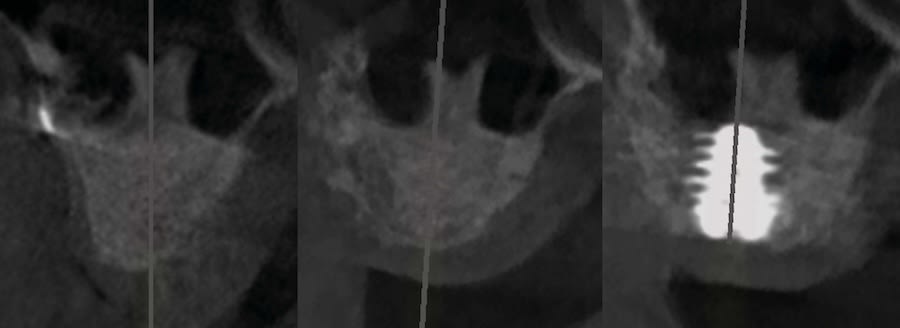

Case 1 (Figure 3 through Figure 24) depicts a 3-year follow-up of combined osseodensification sinus protocol IV in a severely resorbed maxillary ridge with ≤0.5 mm bone height in molar sites and horizontal deficiency at the first premolar site, using a two-stage approach for implant placement.